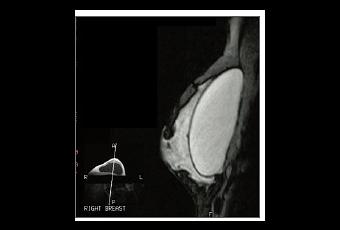

Sources: BAPRAS « BAPRAS speaks out for patients about PIP breast implants” MHRA, The British Association of Aesthetic Plastic Surgeons “Preventative removal of defective implants "not unreasonable" move”, MHRA Poly Implant Prosthese (PIP) breast implants update, Afssaps Synthèse des données Nouvelles recommandations de suivi des femmes porteuses d'implants PIP (Visuel NHS)